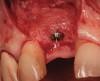

A 53-year-old woman presented with a failing implant in the No. 7 site (Figure 12 and Figure 13). Her desire was to eliminate infection and preserve esthetics. A team effort between the periodontist and restorative dentist to advocate for additional restorative dentistry as well as manage the patient’s expectation of time required was essential. In addition, the patient needed to have realistic expectations of a compromised outcome. Both the restorative dentist and the periodontist informed the patient about the difficulty of achieving this with acceptable esthetic results. Mutual emotional and technical support was required to successfully complete this case, from initial grafting of the defect to placement of anterior restorations (Figure 14 through Figure 23).